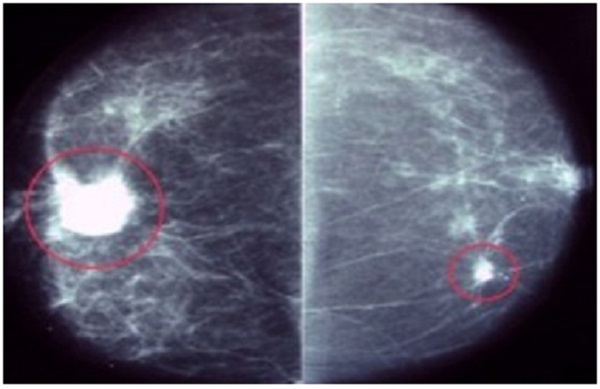

- Chụp nhũ ảnh (Mammogram): Phương pháp này được khuyến cáo là tiêu chuẩn vàng để phát hiện ung thư vú ở giai đoạn sớm. Mammogram có thể phát hiện khối u nhỏ trước khi chúng có thể cảm nhận được qua kiểm tra thông thường.